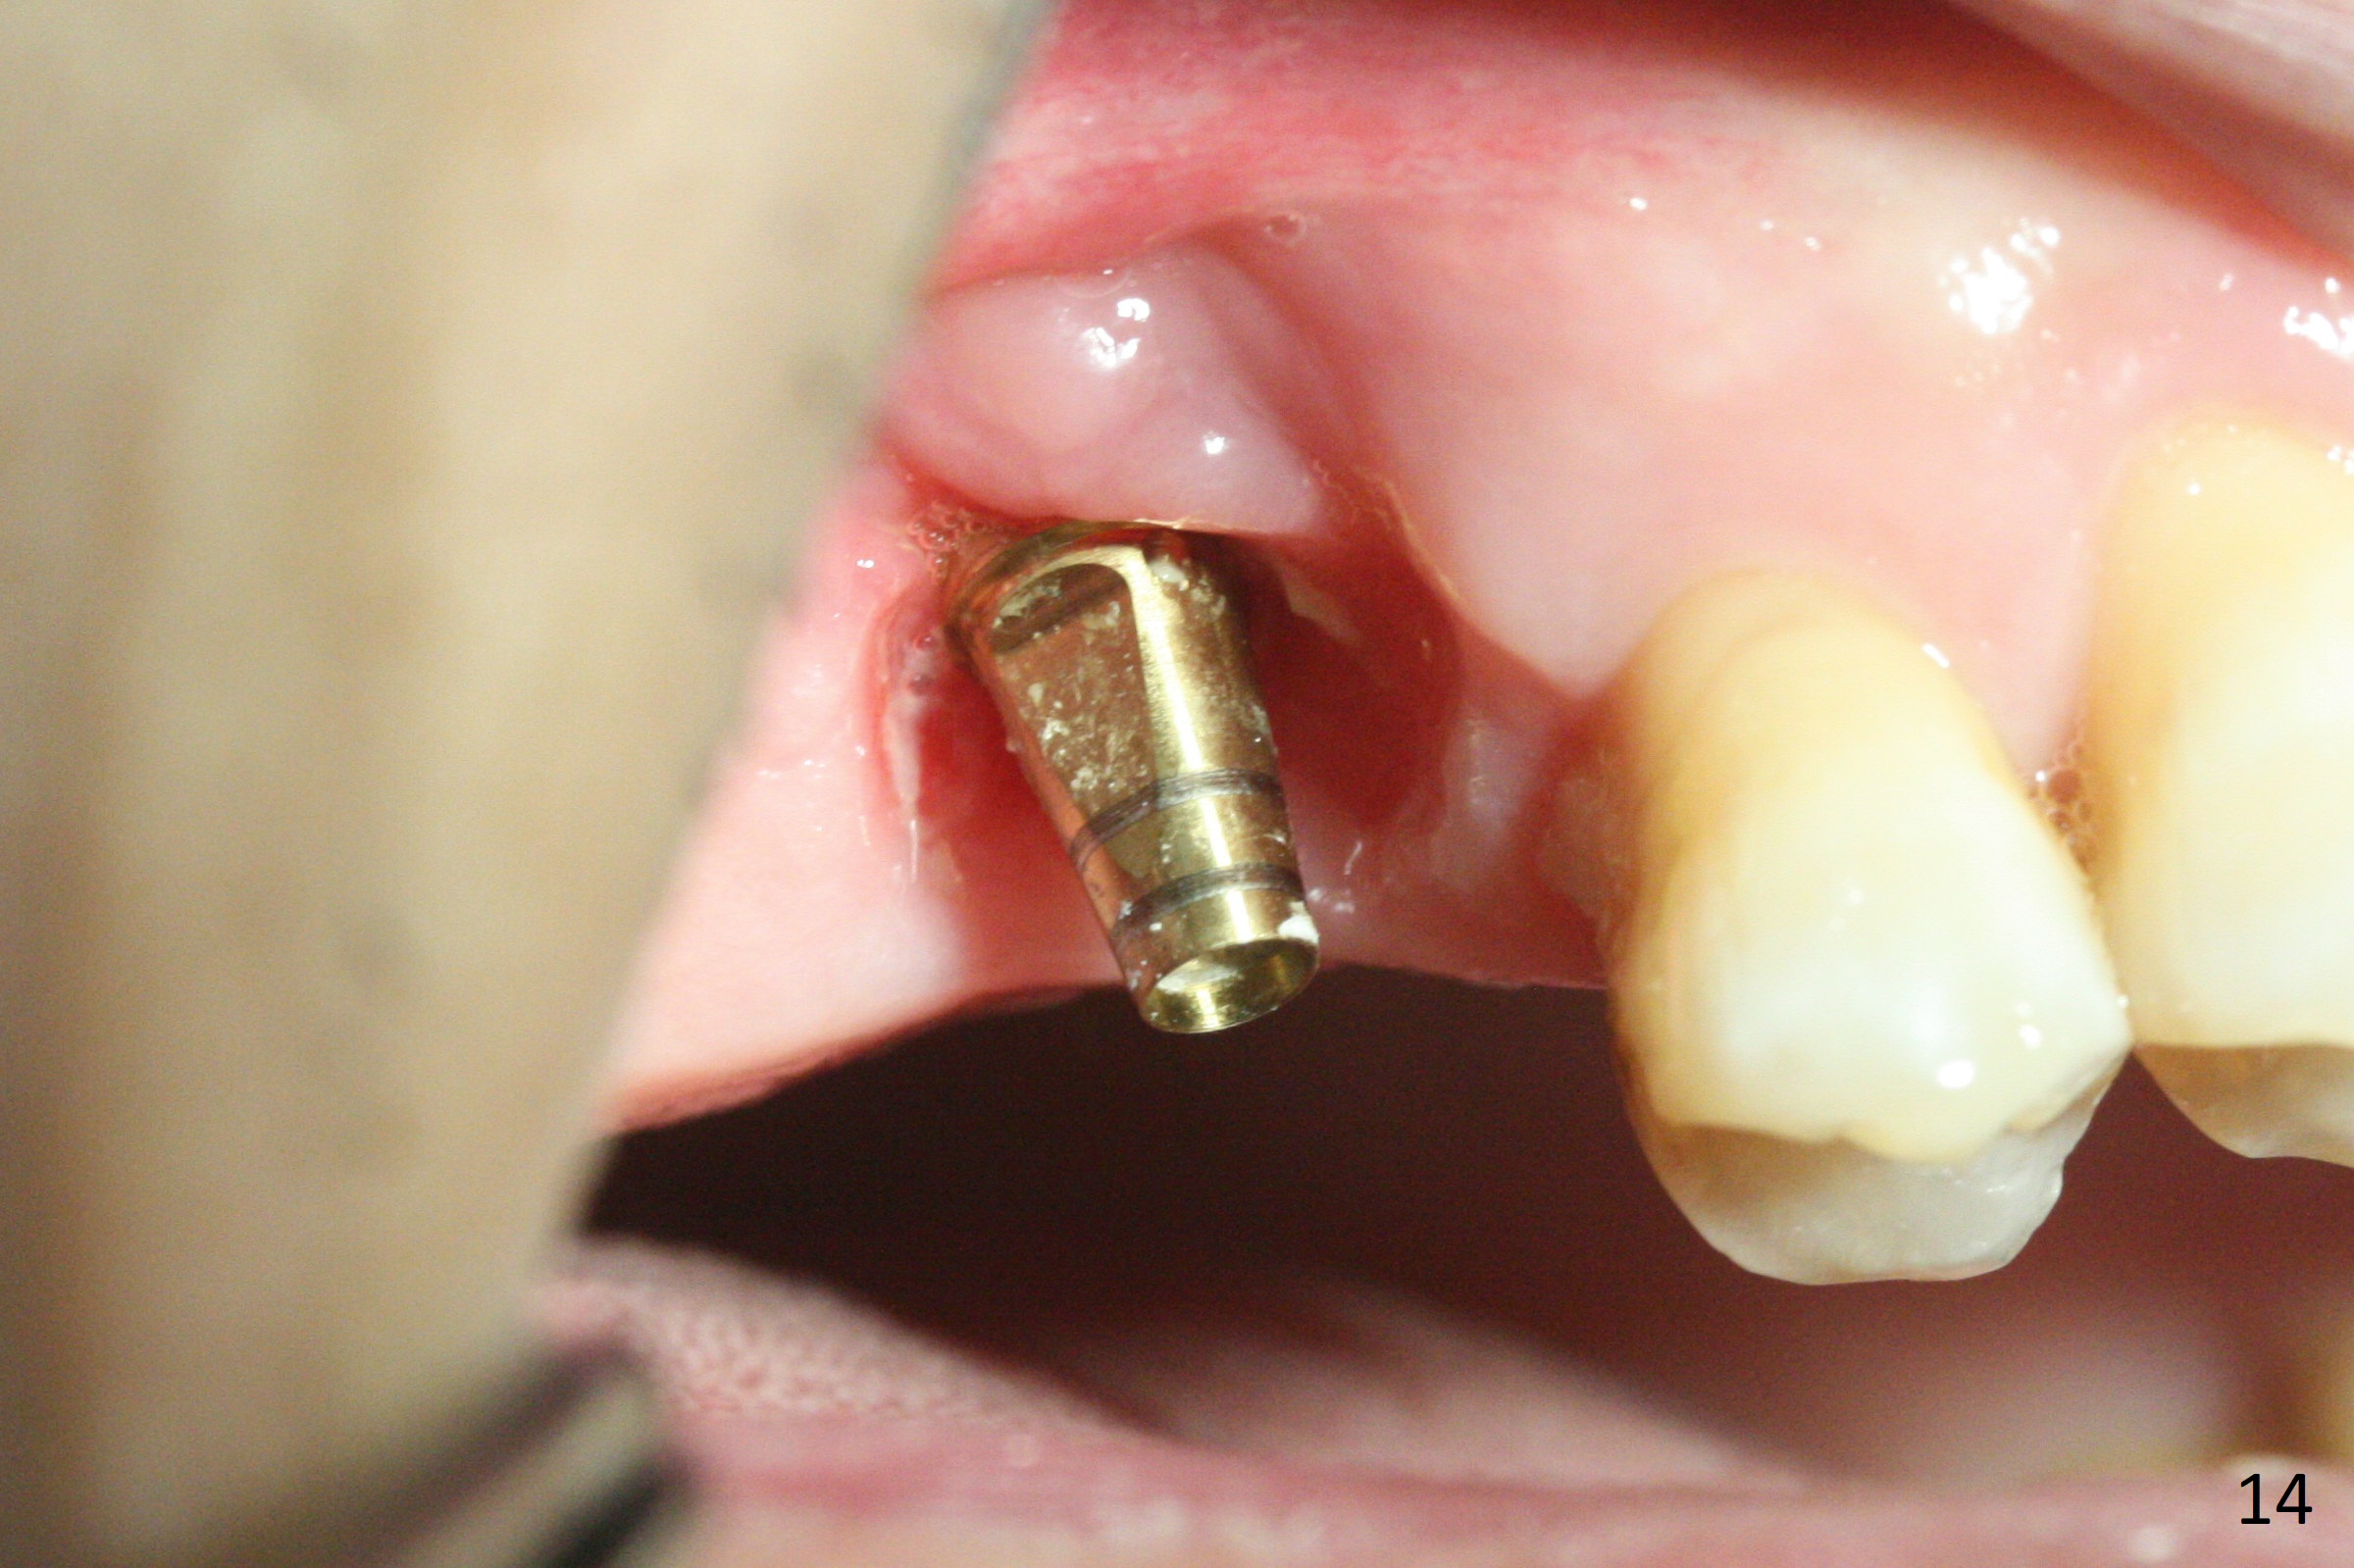

Two weeks later, the buccal gingiva appears to have grown downward (Fig.13). Fig.14 is taken when the provisional is removed. To facilitate this process, change abutment from 4.8x7(3) to (4.5) mm and a new provisional is fabricated (Fig.15): note the metal exposure distobuccally. When the patient returns in another two week, the gap should be able to disappear. There is no loss of bone graft 3 months postop (Fig.16). Two weeks later (3.5 months postop), the margin of the abutment is supragingival buccally and subgingival palatally (Fig.17,18). The gingiva seems to have migrated downward (Fig.19 arrow), while the bone density around the coronal implant appears to increase 5.5 months post cementation (Fig.20). There is buccal swelling with purulent discharge 1.5 years post cementation (Fig.21). Perimplantitis develops. Tuberosis bone graft will be performed when the limited ortho is finished.